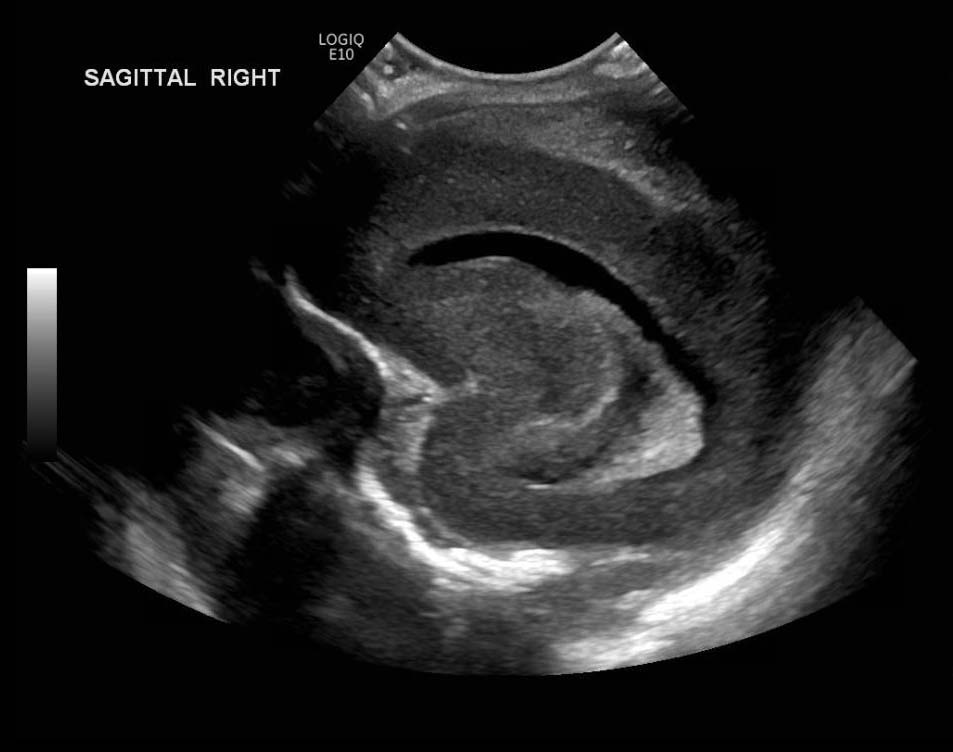

Age: 4 days (born at 24 weeks)

Sex: Male

Indication: Evaluate for germinal matrix hemorrhage

Grade 2 germinal matrix hemorrhage

Sample ReportLeft germinal matrix hemorrhage involving the caudothalamic groove and layering in the occipital horn of the left lateral ventricle without hydrocephalus (grade 2).

No abnormal brain parenchymal echogenicity or extra-axial collections.

Premature sulcation pattern.